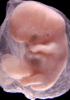

Most embryos at stage 19 are approximately 47-48 post-ovulatory days old and measure 17-20 mm in length. Distinguishing criteria for this stage include straightening of the trunk, the limbs extend nearly directly forward, toe rays are prominent, but interdigital notches have not yet appeared in the foot.

Although some of the photographs below show abnormal embryos, the animations and MRI slice images all depict normal embryos. Abnormal embryos are noted in the titles of the large photos when they are opened.

Photographs